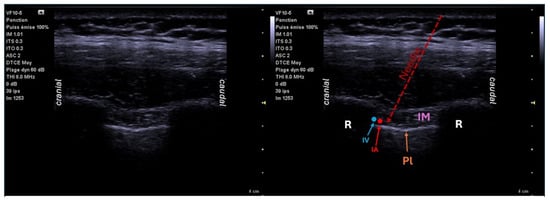

6.3. Intercostal Block